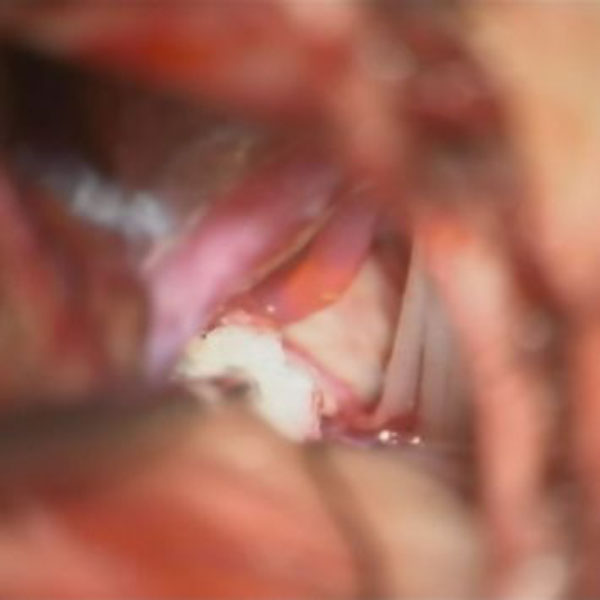

手術中

処置後